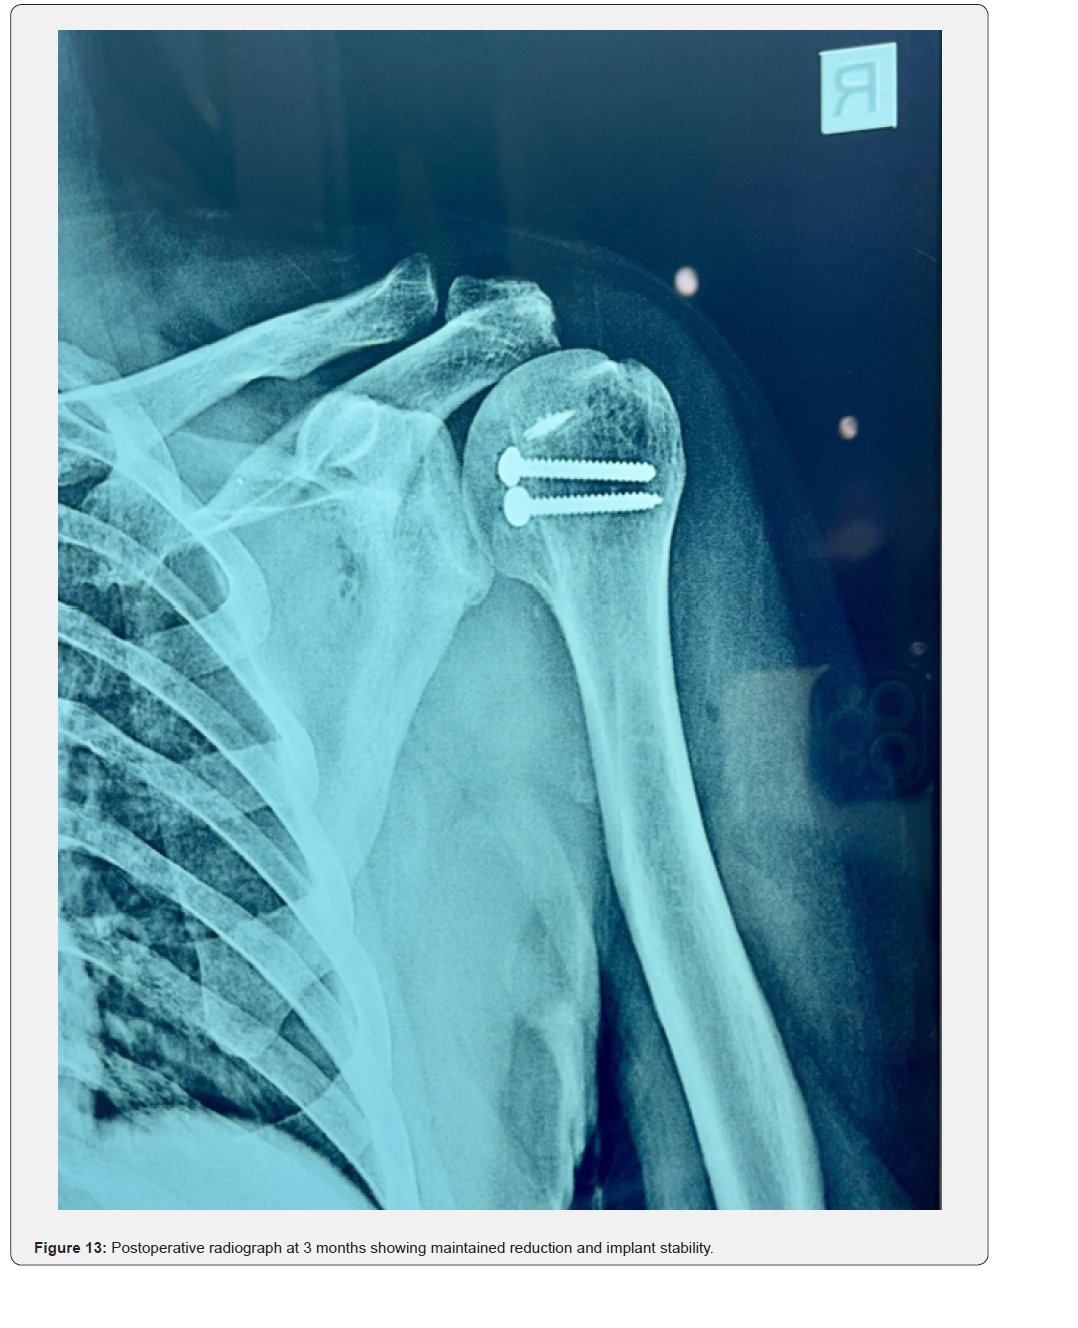

At three months, the patient had regained painless functional mobility with forward flexion to 110°, abduction to 100°, and internal rotation to 25° (Figures 10-12). Postoperative radiographs at three months demonstrated maintained reduction and implant stability without loosening or redislocation (Figure 13). At one-year follow-up, the patient remained pain-free, with forward flexion 140°, abduction 130°, external rotation 20°, and internal rotation 30°. The Constant–Murley score improved from 22 preoperatively to 82, with no evidence of avascular necrosis or post-traumatic arthritis.